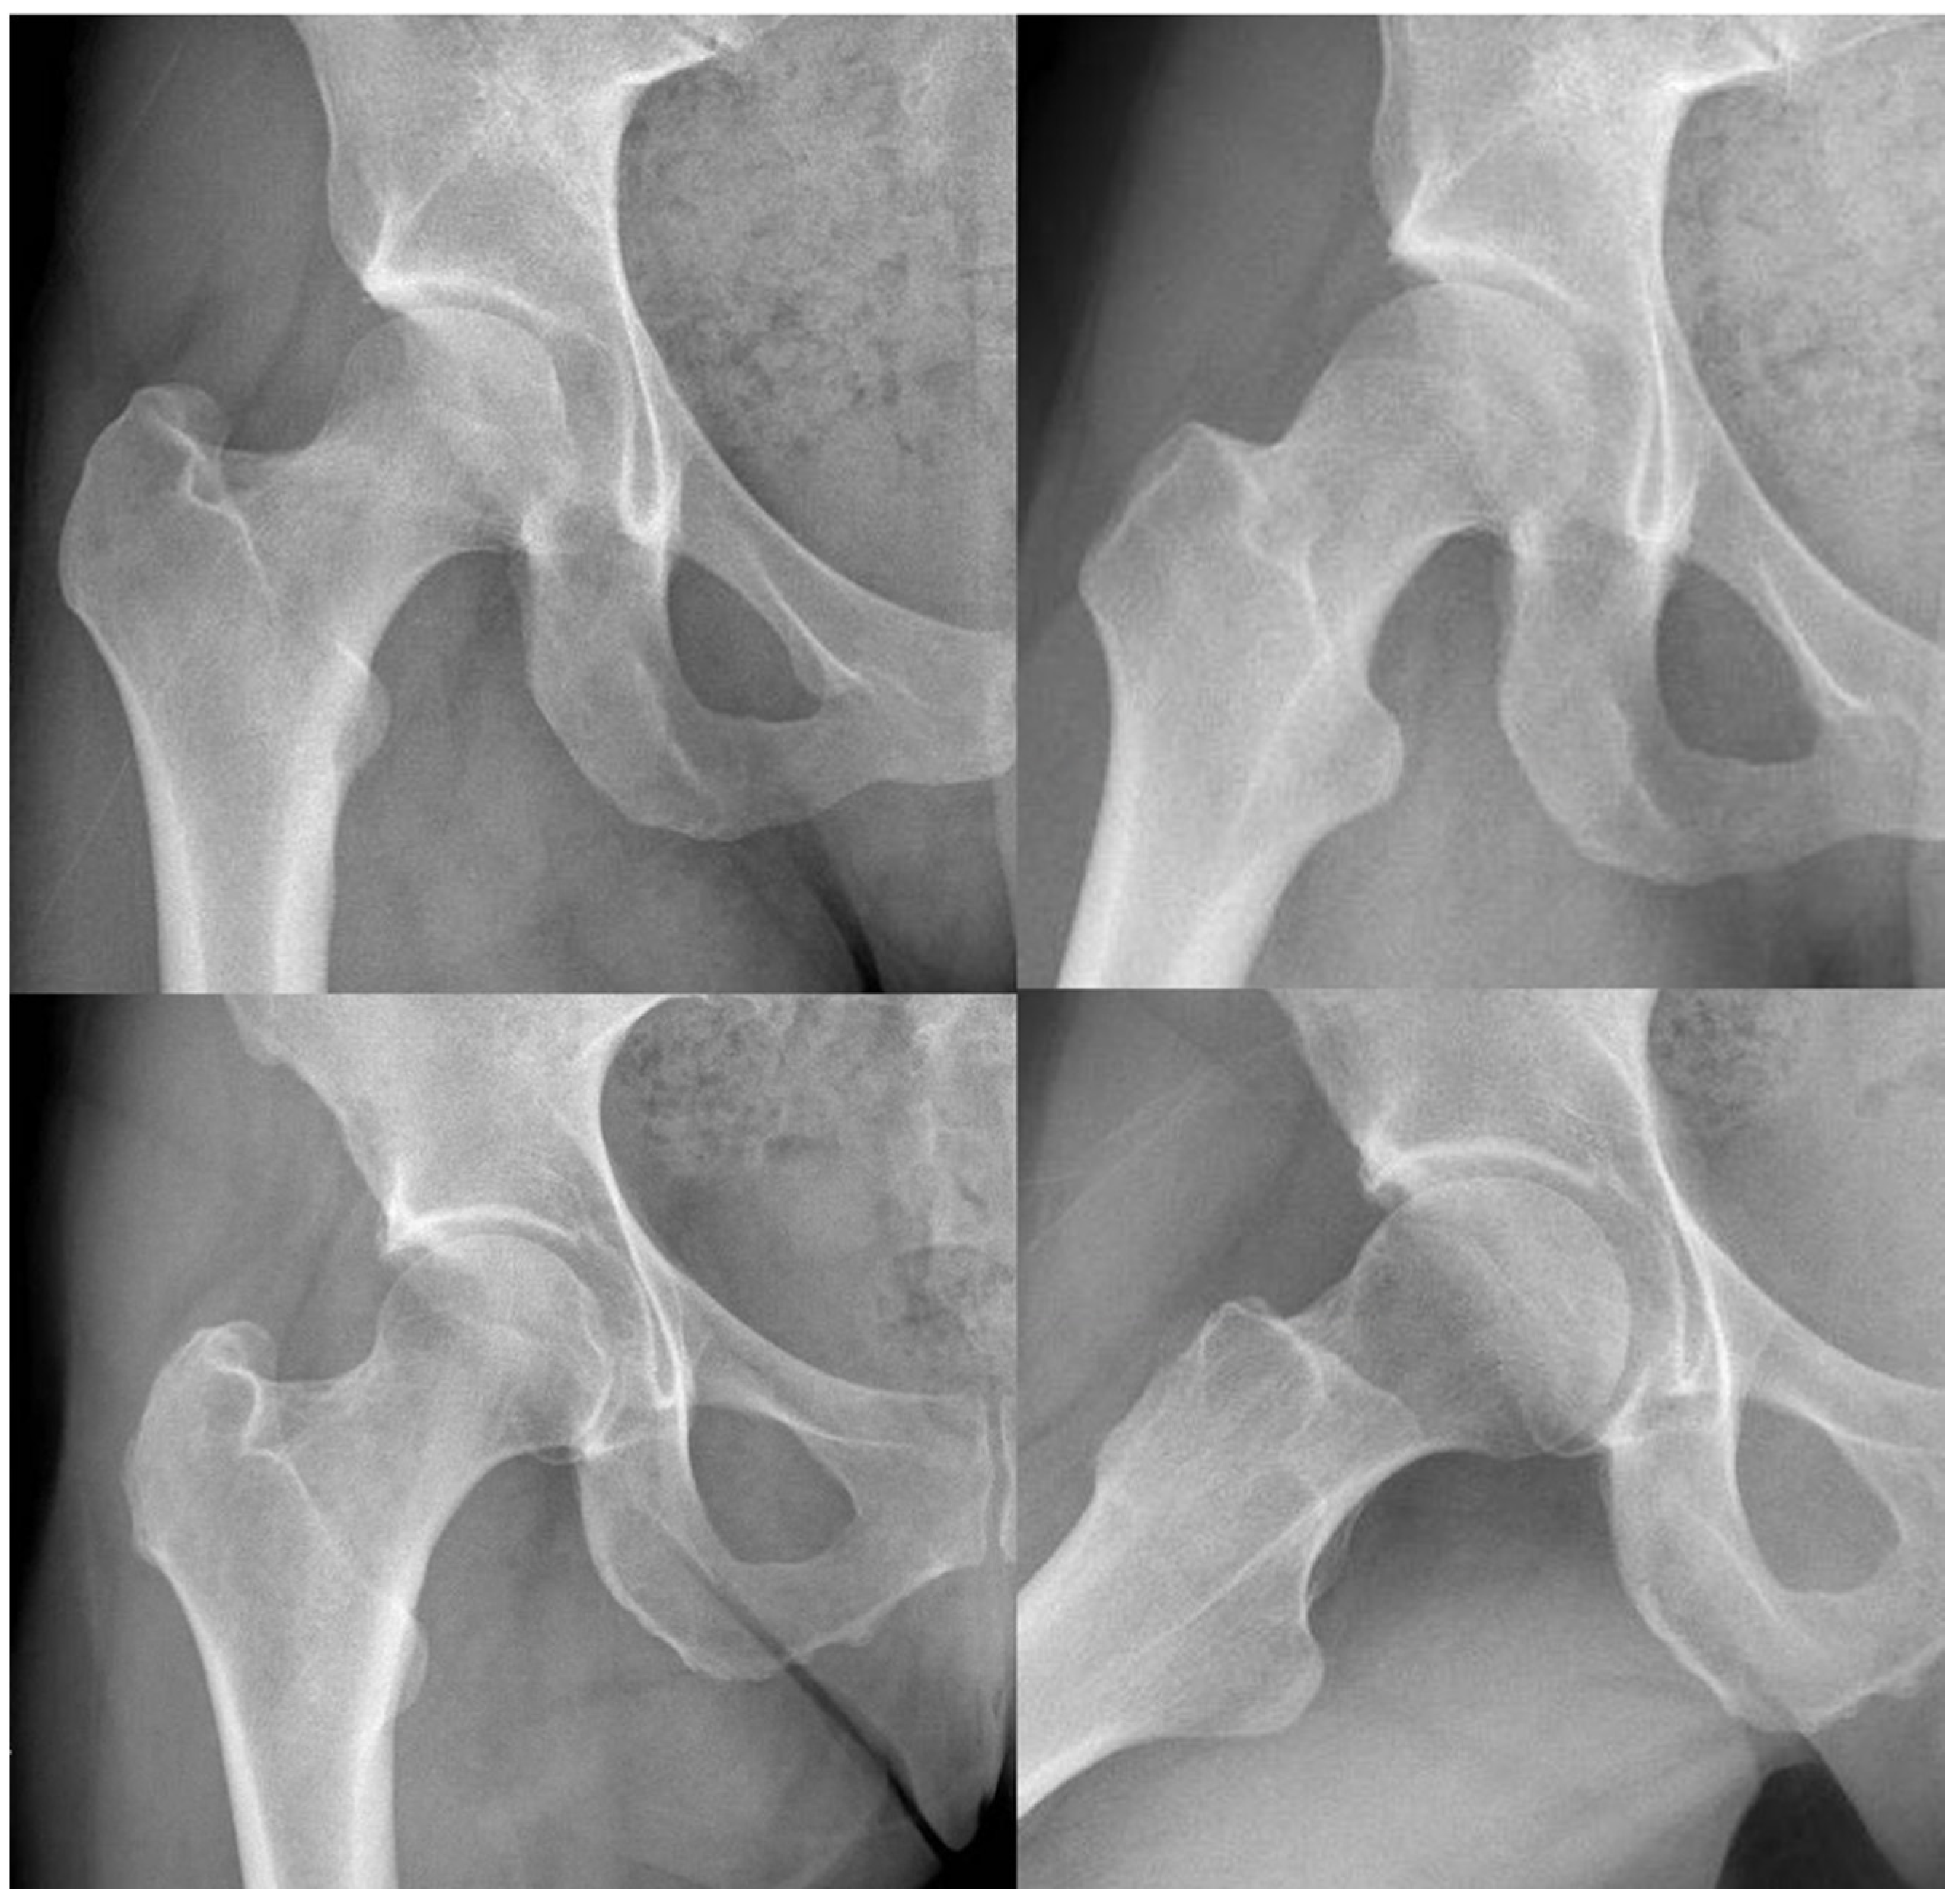

Radiological Measurements

| Wiberg angle (°) | 38.2 (14.21) |

| Acetabular Angle (°) | 10.86 (9.81) |

| Extrusion Index (%) | 18.02 (12.07) |

| Alpha Angle (°) | 68.59 (18.66) |

| Cervical–Diaphyseal angle (°) | 131.45 (8.83) |